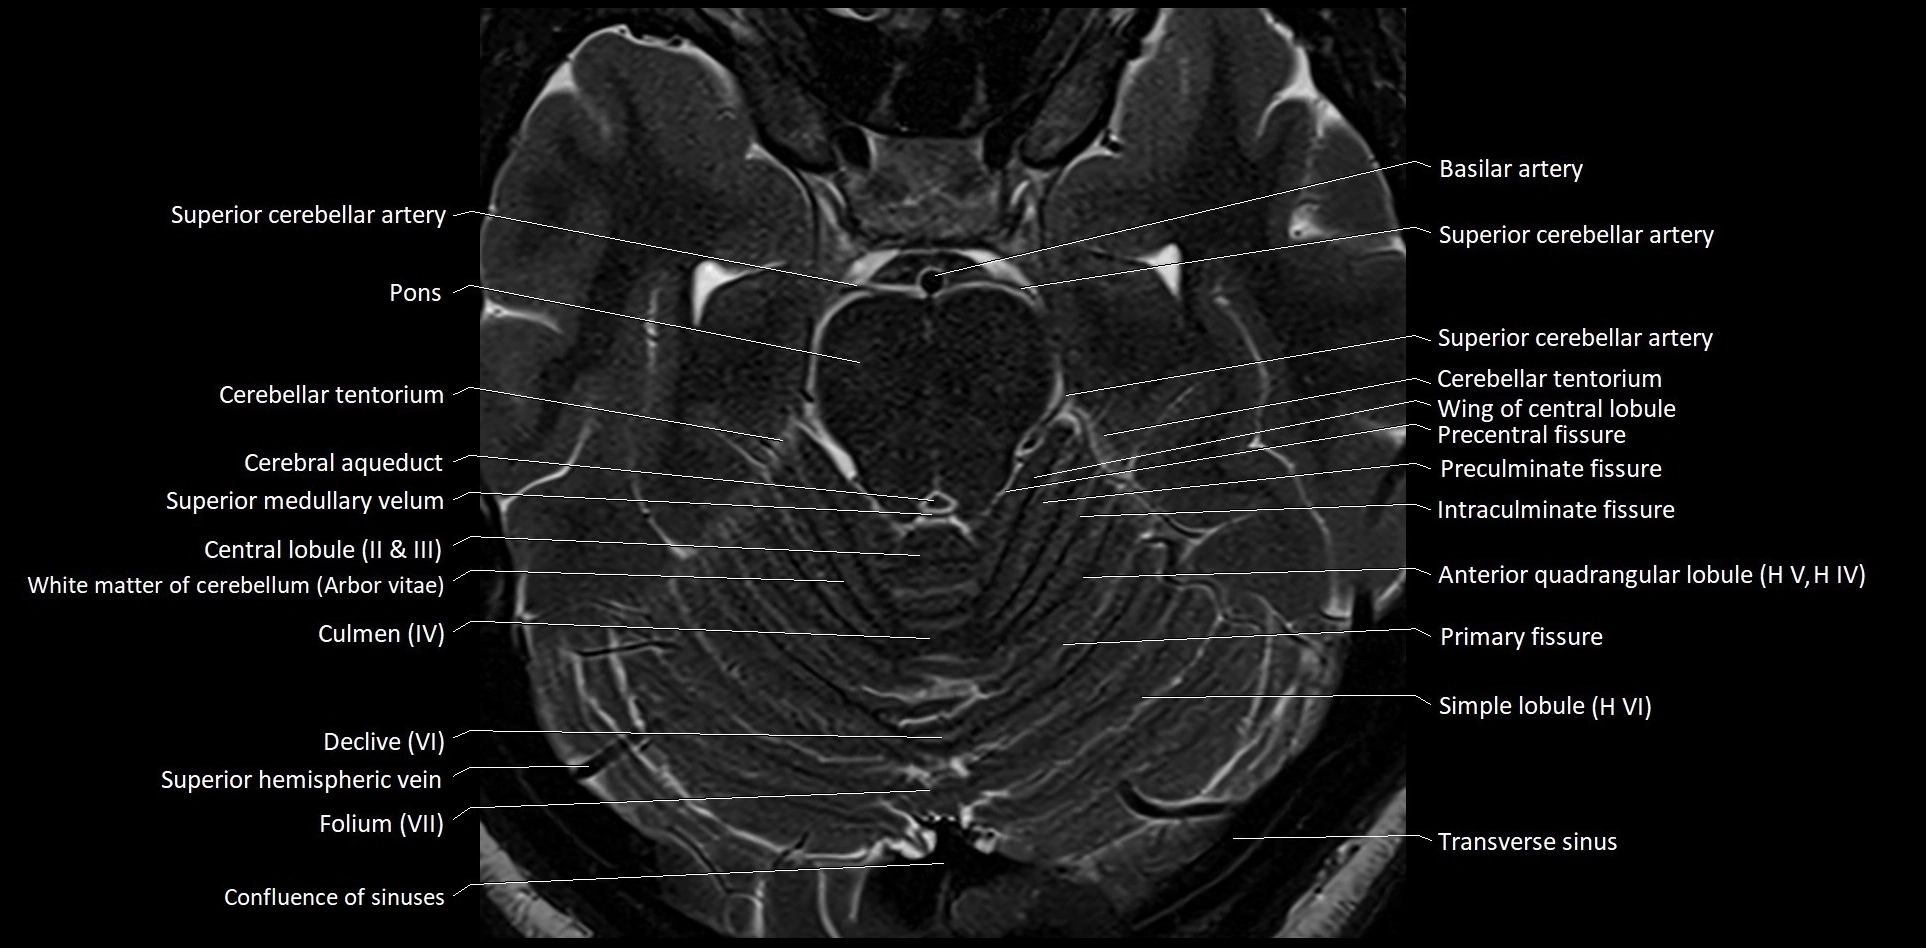

MRI images